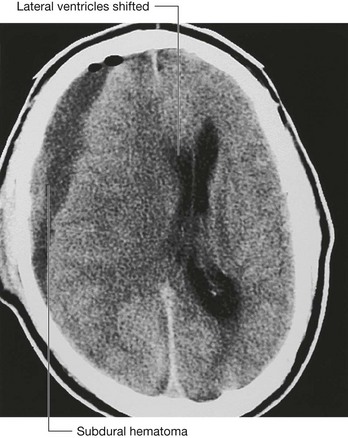

Computed tomography

Since the development of the first computed tomography (CT) scanner, cerebral CT has been the “workhorse” of neuroradiological examination. It is ideally used for head injury because the brain and its coverings can be easily and quickly examined and blood is easily detected. By altering the mathematical algorithm of the data set the bones can also be demonstrated.

With intravenous contrast, CT angiography can be used to demonstrate the position and the size of an intracerebral aneurysm before endovascular treatment.

In the clinic

Fractures of the skull vault and extradural hematoma

The skull vault is a remarkably strong structure—and quite rightly, because it protects our most vital organ, the brain. The shape of the skull vault is of critical importance and its biomechanics prevent fracture. From a clinical standpoint skull fractures alert clinicians to the nature and force of an injury and potential complications. The fracture itself is usually of little consequence (unlike, say, a fracture of the tibia). Of key importance is the need to minimize the extent of primary brain injury and to treat potential secondary complications, rather than focusing on the skull fracture. Skull fractures that have particular significance include depressed skull fractures, compound fractures, and pterion fractures.

Depressed skull fractures

In a depressed skull fracture a bony fragment is depressed below the normal skull convexity. This may lead to secondary arterial and venous damage with hematoma formation. Furthermore, a primary brain injury can also result from this type of fracture.